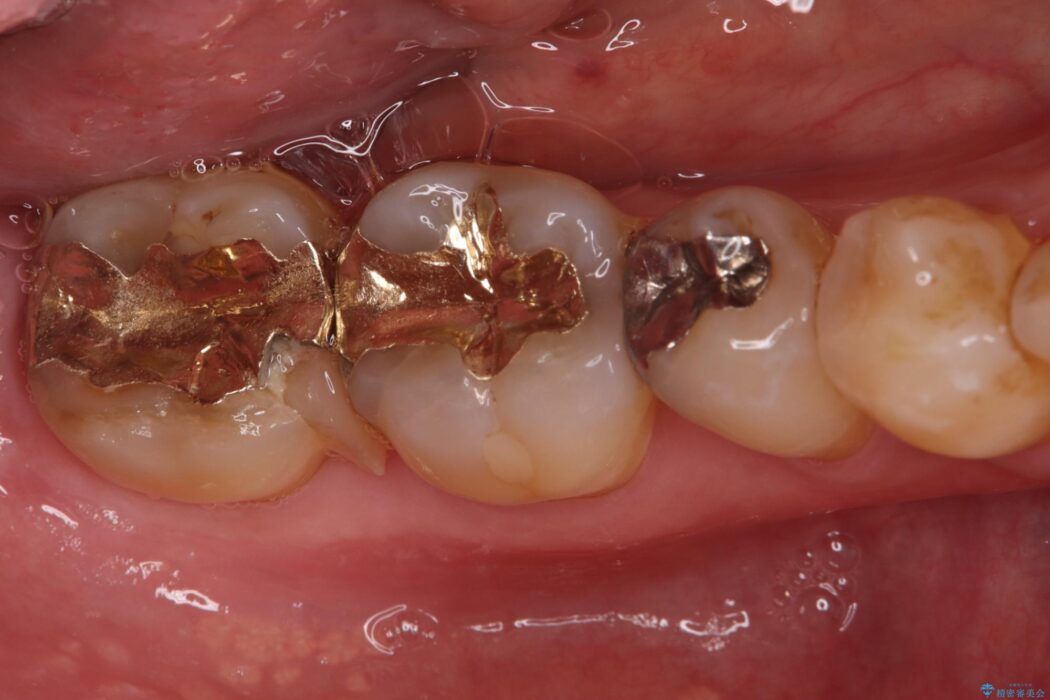

以前治療した奥歯(右下7番)の詰め物が欠けてしまったとご来院された患者様です。

検査の結果、残存歯質が少なく破折リスクが高いため、歯全体の補強が必要と診断しました。強い咬合力に耐えられるよう、適合性と強度に優れたPGAクラウンによる修復を計画しました。これにより、二次カリエス(虫歯の再発)や破折を防ぎ、奥歯の機能を長期的に安定させます。

欠けた奥歯を土台から整え、金主成分の「PGAクラウン」で修復しました。PGAクラウンは、金を主成分とする合金でできており、非常に優れた特性を持っています。

欠けてしまった歯の構造的な弱点が解消され、患者様は硬いものでもしっかりと噛める、安心で機能的な奥歯を取り戻すことができました。